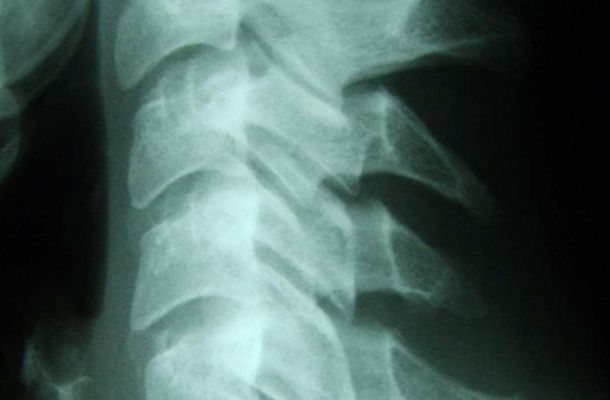

Vor jeder Behandlung steht die genaue Diagnose: Art und Ursache der Störung werden genau untersucht und Beschwerden ausgeschlossen, die nicht mit Chiropraktik behandelt werden können. Dazu werden auch weiterführende Abklärungen wie Röntgen oder Magnetresonanztomografie (MRI) durchgeführt.

Viele Beschwerden haben ihren Ursprung in der Wirbelsäule. Die Chiropraktorin oder der Chiropraktor ist die erste Anlaufstelle, wenn der Körper schmerzt.